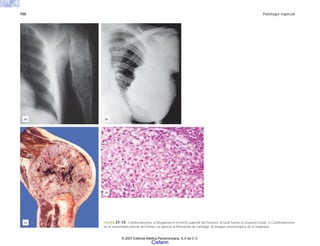

FIGURA 6-14. Tuberculosis. a) Tuberculosis pulmonar primaria progresiva con lesión

destructiva de aspecto caseoso en el parénquima del pulmón derecho y en los ganglios

peritraqueales. b) Mal de Pott. Destrucción de las vértebras con colapso de las mismas,

deformidad de la columna y compresión medular. c) Tuberculoma en el tallo cerebral. Masa

ocupativa bien delimitada de aspecto caseoso.

(d)

(f)

(e)

FIGURA 6-14B. d) Meningitis tuberculosa. Exudado blanquecino en la base

del encéfalo rodeando y ocluyendo las cisternas basales. e) Tuberculosis intes-

tinal con lesiones ulceradas en la mucosa del ileon. f) Adenitis mesentérica con

necrosis caseosa.